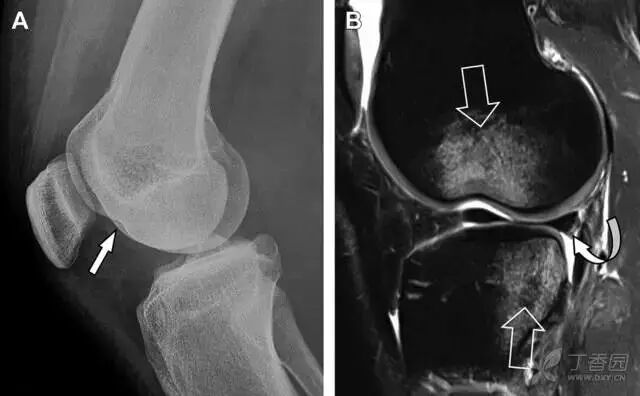

图 2 扭伤后的股骨外侧髁凹陷征

A 侧位片示股骨外侧髁凹陷。B MRI 矢状位 T2 加权像示股骨外侧髁及胫骨后外侧骨挫伤(空箭头)。胫骨近端随着后交叉韧带撕裂发生移位,露出外侧半月板的后角(弧形箭头)。